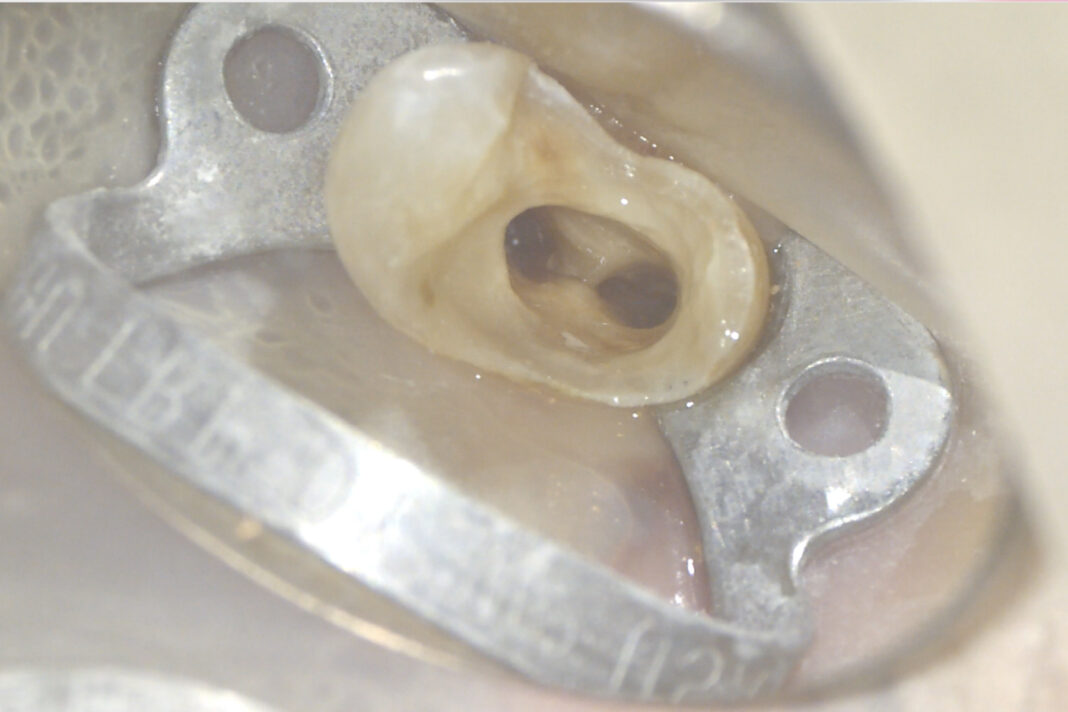

Visualizzata la guttaperca intracanalare con core plastico (Figura 4) viene completato lo svuotamento dei canali (Figura 5) mediante strumenti rotanti Protaper Gold (Dentsply-Sirona); effettuata la misurazione elettronica della lunghezza di lavoro, si procede con la strumentazione degli interi canali con tecnica step-down.